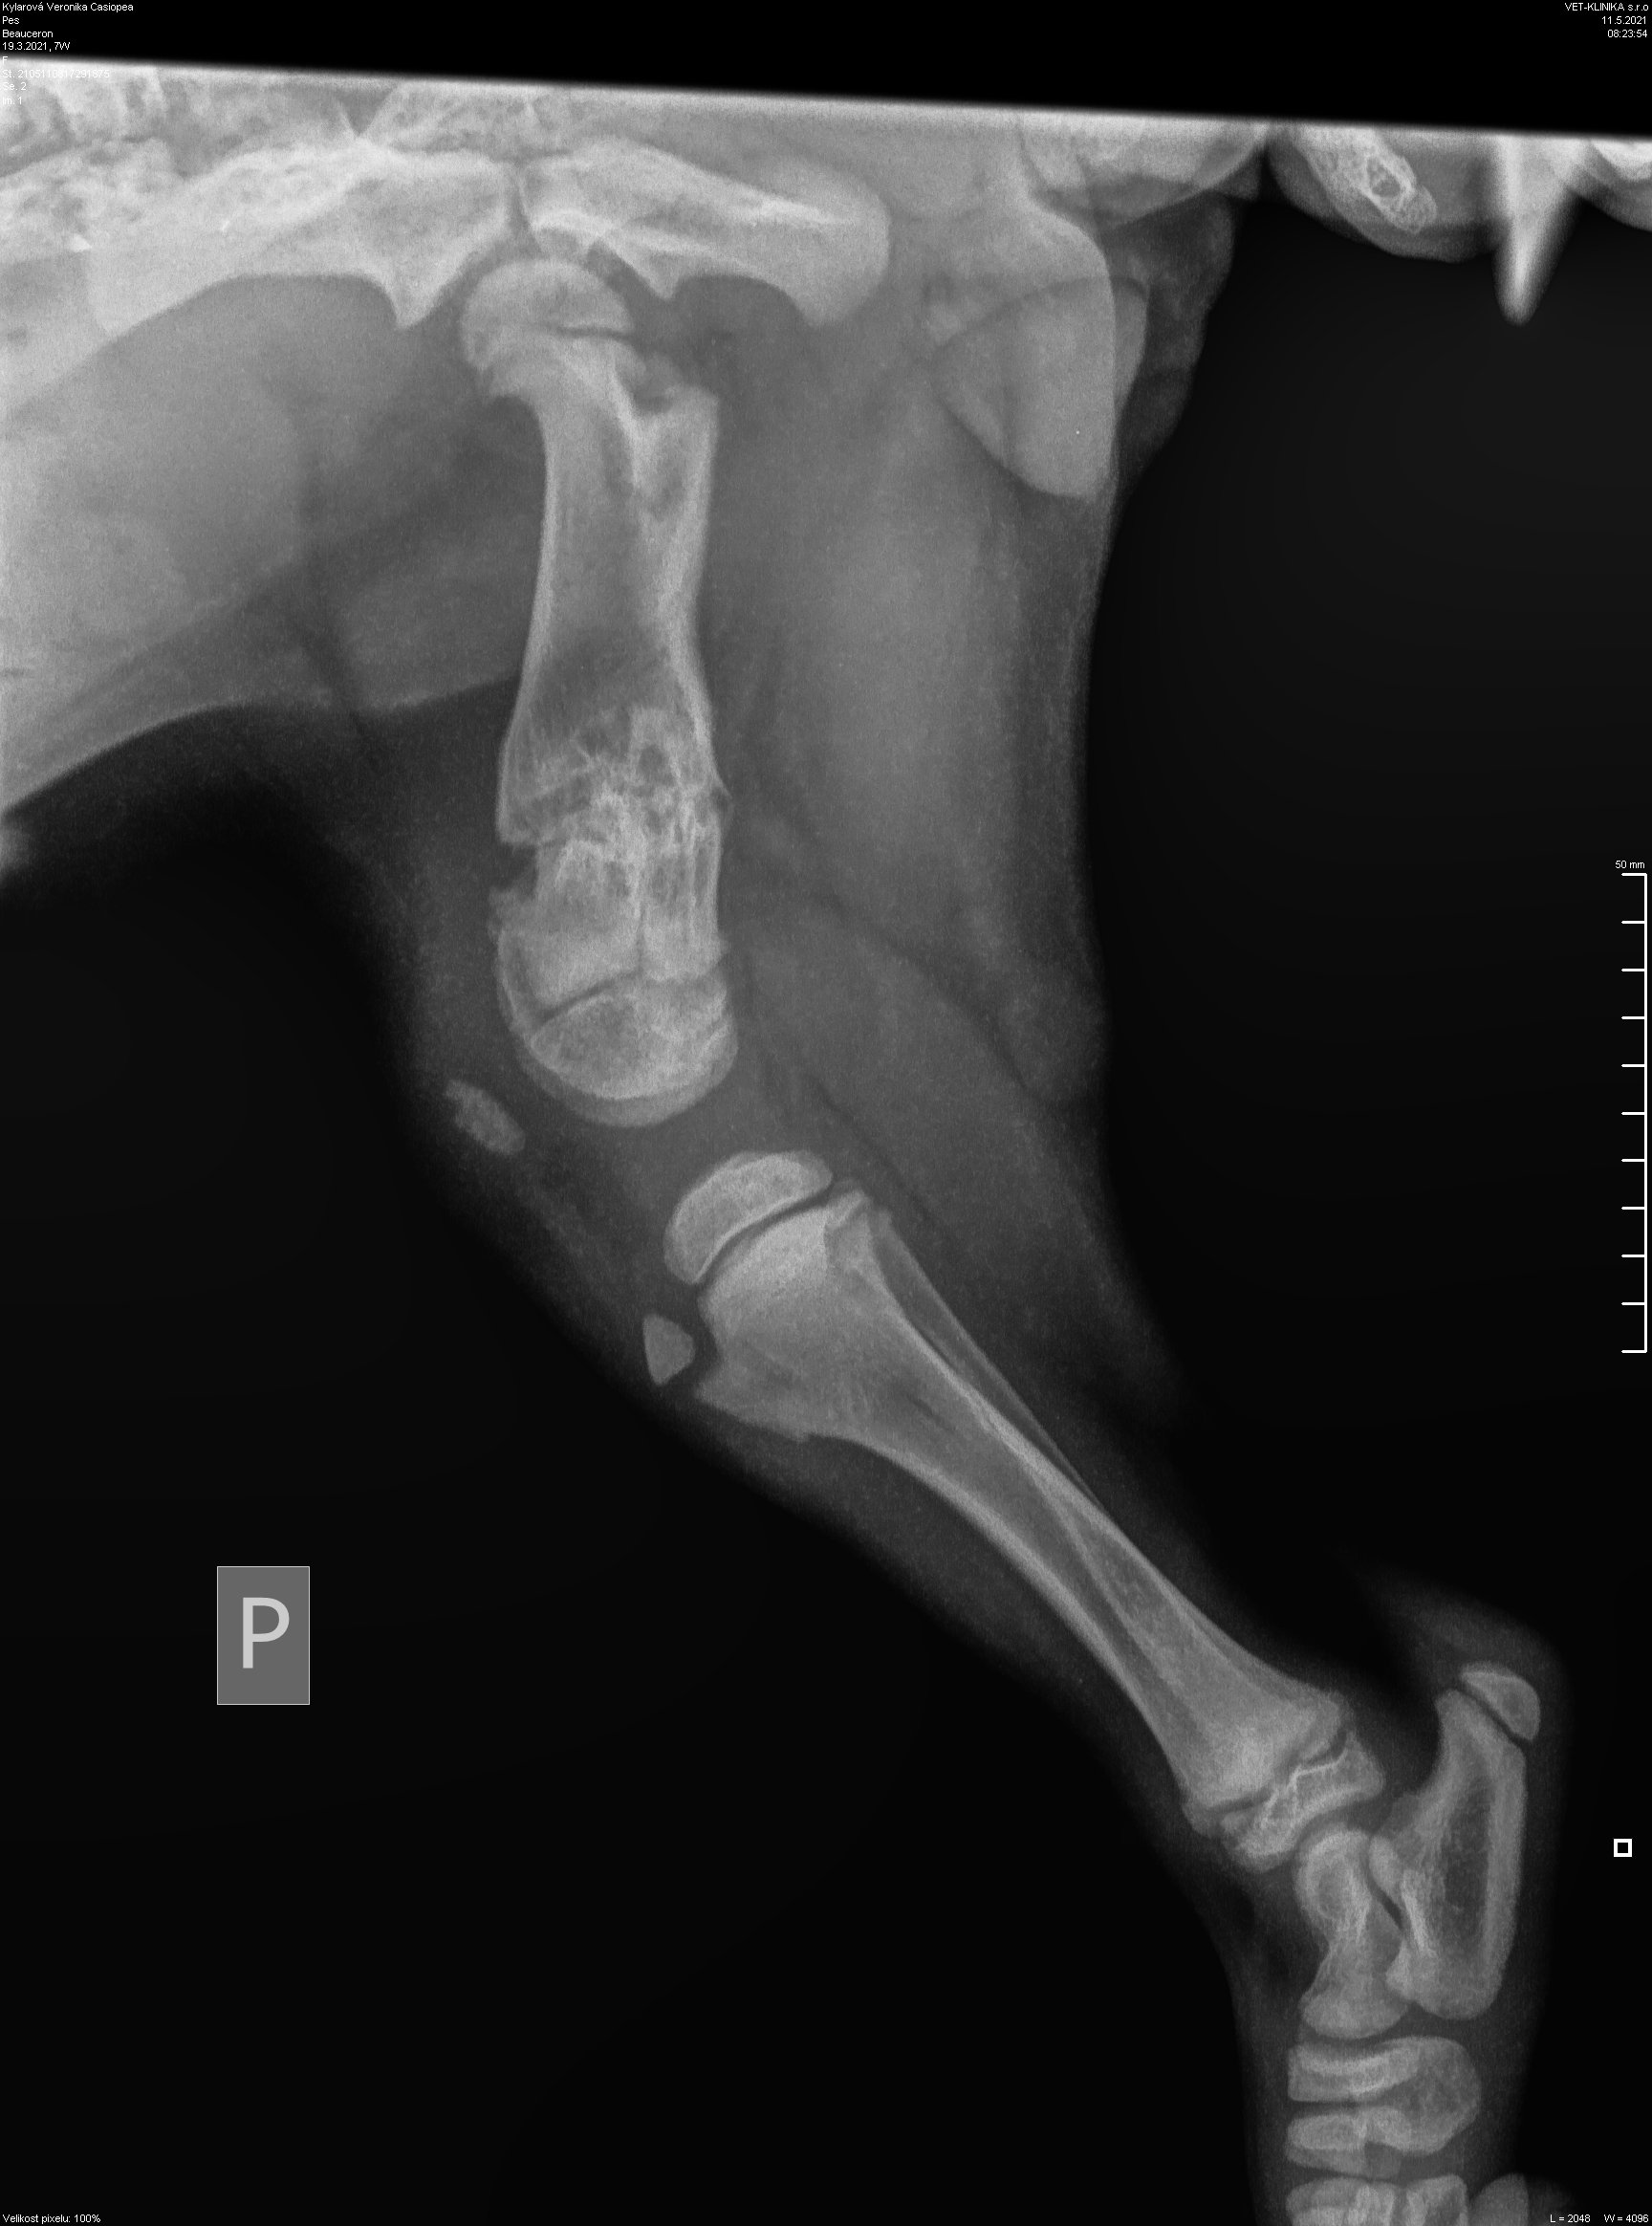

Dobrý den, chtěla bych radu ohledně zlomeniny i téměř 8.tydeniho štěněte. Byla zjištěna fraktura stehenní kosti, bohužel jsem se toho moc nedozvěděla.Zajimala by mne jeli to vážné?Může mít zvíře do budoucna nějaké potíže? Popřípadě doporučily by jste operaci?Či se to zahojí samo bez následků? Děkuji

Dobrý den, u psů a koček se zlomeniny řeší chirurgickou cestou, aby došlo k bezproblémovému srůstu kostí. Bandáže nebo obvazy jsou jen dočasným řešením před chirurgií. Žádný obvaz není schopen stabilizovat zlomeninu tak dobře, aby mohl pejsek končetinu používat. Proto se přistupuje k chirurgické fixaci zlomenin. Dle plemene štěněte se poté volí vhodná chirurgie - jinak se řeší zlomenina u malého plemene a jinak u plemene velkého, které rychle roste. Určitě navštivte veterinární pracoviště, které je dostatečně vybaveno pro tyto operace. S pozdravem MVDr. Orlovská